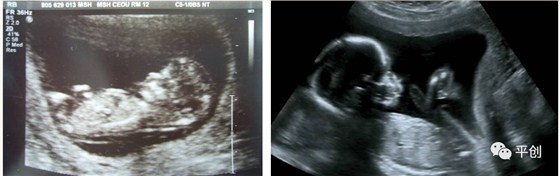

更準確的醫學診斷,來自B超檢查結果的輔助,準確的B超檢查結果,來自B超醫生看到的B超圖像,清晰的B超成像,來自好的耦合劑。所以說,好的耦合劑對B超的成像很重要。

而影響B超檢查成像的因素有兩點,一是來自好的探頭,二是來自優質的耦合劑。如果這兩個產品其中有一個質量不過關,即對B超成像有一定程度的影響,可能會有成像不清楚,醫生無法準確判斷所檢查器官的實際病變,嚴重的有可能度至醫生誤診的后果。

我今天要說的是:耦合劑對B超成像的影響。

所生產出來的耦合劑無雜質、透明度高、不易干,不化水,易偶合、易擦凈,透聲性超過國家標準的50%(數據通過國家指定的第三方檢測機構檢測結果所得),完全地解決了成像不清晰的難題。